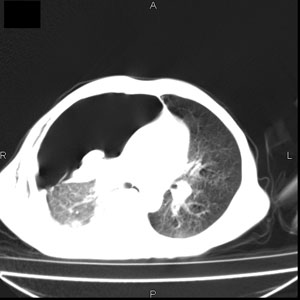

患者男,77岁,于3日前从树上摔下,头部查ct示蛛血,硬膜下出血,上腹部ct未见明显异常,右侧胸腔积液,左侧如常。肺部拍片示右侧肋骨多发骨折住院后今日来查肺部ct,我看到的是1。右侧胸腔血气胸并右肺上叶,中叶压缩性肺不张,2。右肺下叶肺挫伤并多发肋骨骨折,肌内及皮下积气3。左侧少量胸腔积液,我想请教的是3天前左侧胸腔里没有积液今天怎么出现了呢,是什么原因呢?请讨论。

支持楼主意见。外伤可有迟发性的改变。

考虑外伤性迟发性胸腔积液。